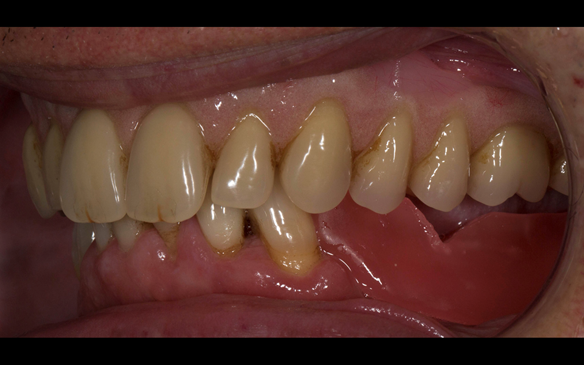

10 years prior to consultation the patient's general dentist diagnosed periodontitis and referred him to Manchester Dental Hospital. He received a treatment plan to manage the periodontitis. Unfortunately, this was not acted on. Four years ago gaps developed between the upper front teeth. Orthodontic treatment was provided to align the teeth. A bonded retainer was fitted onto the upper front teeth. Approximately one year prior to consultation with me the patient noticed the teeth moving again. He consulted his orthodontist, who advised no further orthodontic treatment. One month prior to the consultation with me the upper left central incisor fell out whilst eating.

- Generalised periodontitis; stage IV grade C: currently unstable, risk factors: smoker.

- The remaining maxillary teeth had hopeless prognosis in the short term. They exhibited 80 - 100% alveolar bone loss with increased mobility (Grade 2 - 3).

- The remaining mandibular teeth had approximately 30 - 50% alveolar bone loss with grade 1 mobility.